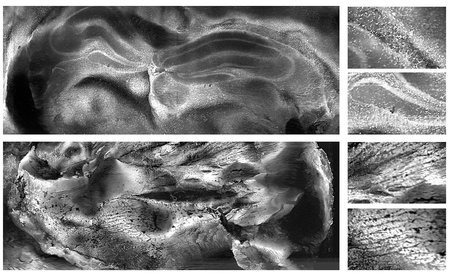

These images show the high resolution achieved with the new microscopy technique. A mouse brain cross-section as seen with photoacoustic imaging is shown in the upper left image, with two detailed close-ups displayed to the right. A mouse heart cross-section captured with the same technique is shown below, with two close-ups shown to the right.

Credit: Cao, R. et al. Science Advance, 2024. Caltech